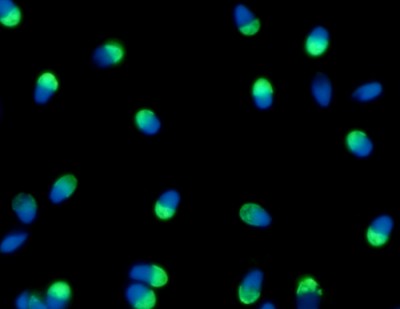

Implementan en la Argentina una novedosa técnica que selecciona los espermatozoides sanos , ya hubo más de cien nacimientos

Ciencia y tecnología